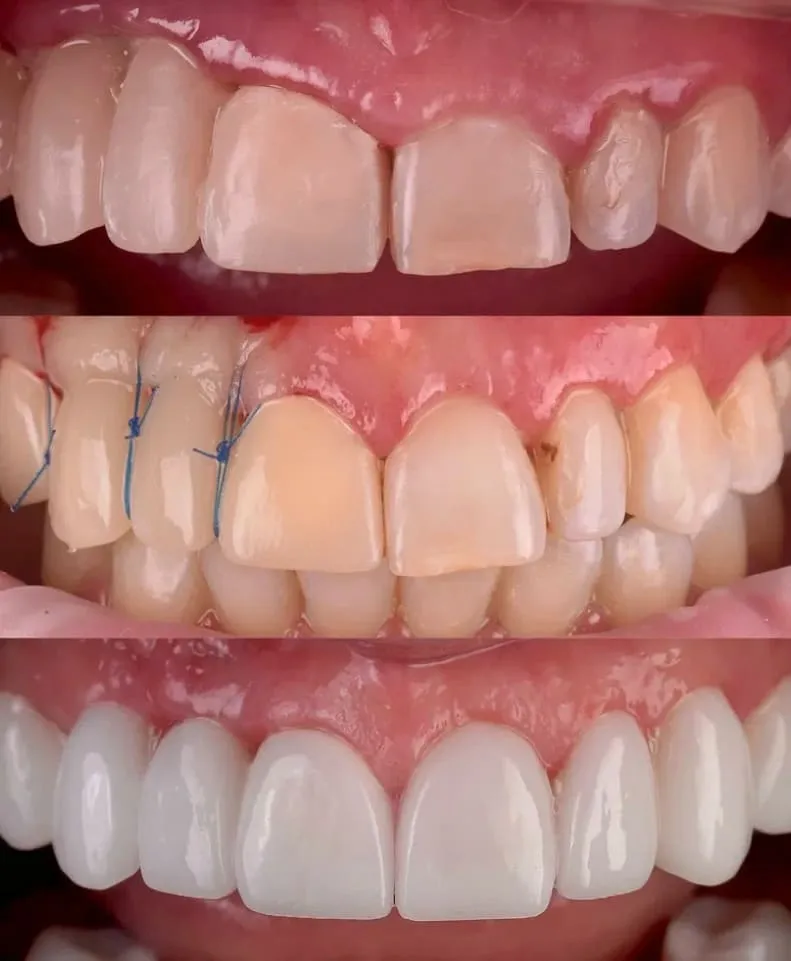

Gum plastic surgery